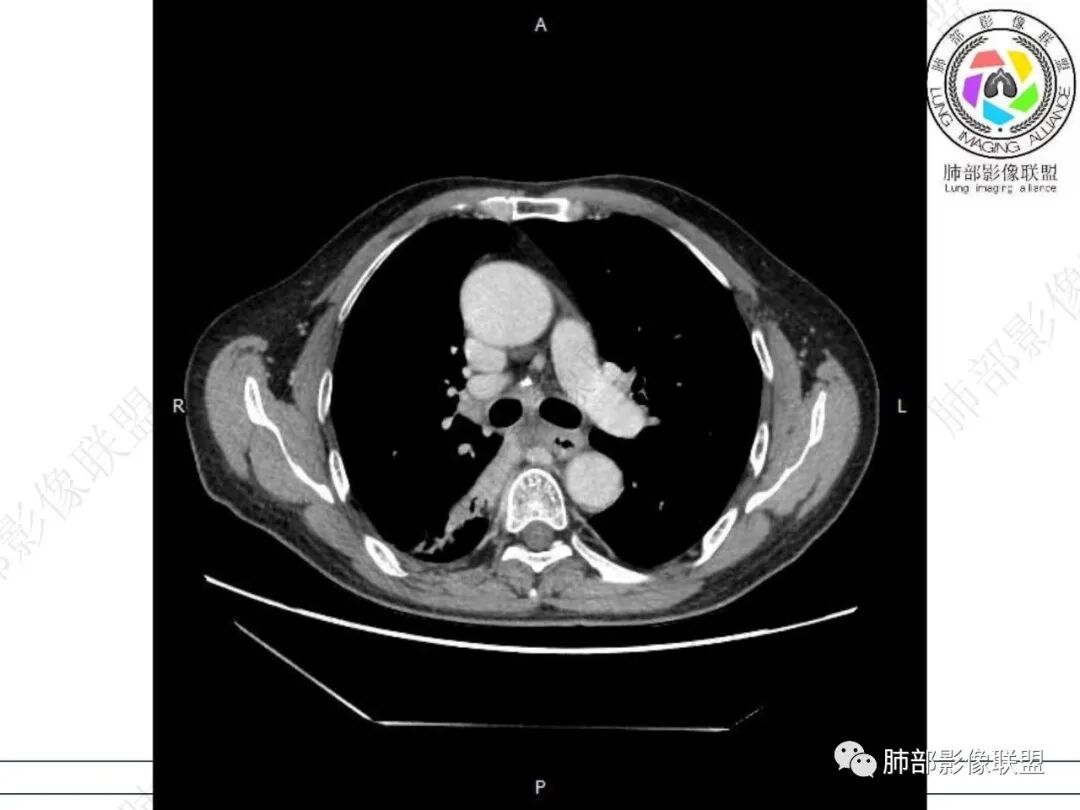

右肺下叶背段可见斑片状、条片状高密度影,支气管扩张,周围伴有磨玻璃影,边界欠清,纵隔窗:可见脊柱偏右侧可见斑片状影,与食管交界面欠清,食管形态不规则,考虑食管支气管瘘?食管异物穿孔?支气管异物?建议食管镜及支气管镜检查。

气管隆突下团片影,其内积气,与食道分界不清,食道壁增厚,管腔狭窄,右下肺实变影,支气管壁增厚,考虑食管支气管瘘并右下肺感染,食道肿瘤病变不除外

支持食管支气管瘘(考虑食管癌)伴后纵隔及右肺感染,食管管壁明显增厚,管腔狭窄,相邻右侧后纵隔内软组织内可见气体影,与食管分界不清,右肺有实变及不张。

右肺下叶背段条片状实变影,内可见支气管走行,支气管有狭窄有扩张,周围可见磨玻璃影,隆突下团片影,内密度不均可见气体影,与周围结构界限不清。食管下段壁增厚,管腔狭窄,右肺下叶慢性炎、肺不张,考虑食道肿瘤所致气管食管瘘。

右肺下叶沿肺叶肺段分布斑片、条片状影,以下叶背段为显,边缘模糊,内可见支气管走行,局部支气管管壁增厚,右侧胸腔少量积液。纵隔隆突下可见不均匀软组织密度影,与周围结构分界不清,内见气体密度影,与食管及相邻右肺支气管之间未显示通道。邻近食管下段壁明显不规则增厚,增强后食管管壁明显不均匀强化,可见线样强化的连续完整粘膜影。